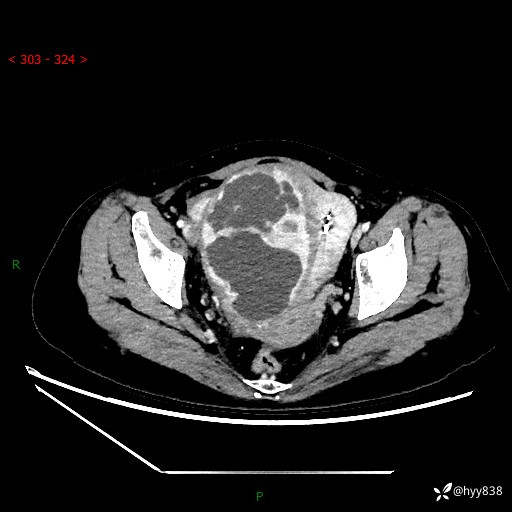

辅助检查:CT

盆腔CT平扫

增强(动脉期+静脉期)